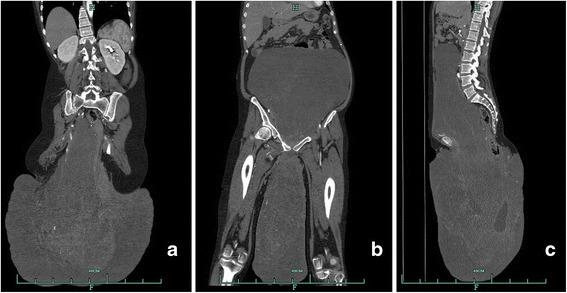

The case reported is of a patient presenting with a solitary giant retroperitoneal neurofibroma that threatened to obliterate both peritoneal and pelvic cavities and protruded conspicuously into the right gluteal region. The enormous dumbbell-shaped mass was surgically removed in three parts. Postoperative pathology studies confirmed a diagnosis of neurofibroma. Follow-up computed tomography images taken three months postoperatively revealed residual tumor in the perianal region. The patient's quality of life had measurably improved on follow-up at eight months.

报道的病例为一名患者,患有孤立性巨大腹膜后神经纤维瘤,该肿瘤几乎占据了整个腹腔和盆腔,并明显突出至右侧臀区。通过手术分三个部分切除了巨大的哑铃形肿块。术后病理研究确诊为神经纤维瘤。术后三个月的计算机断层扫描图像显示肛门周围区域有残留肿瘤。在八个月的随访中,患者的生活质量有了明显改善。